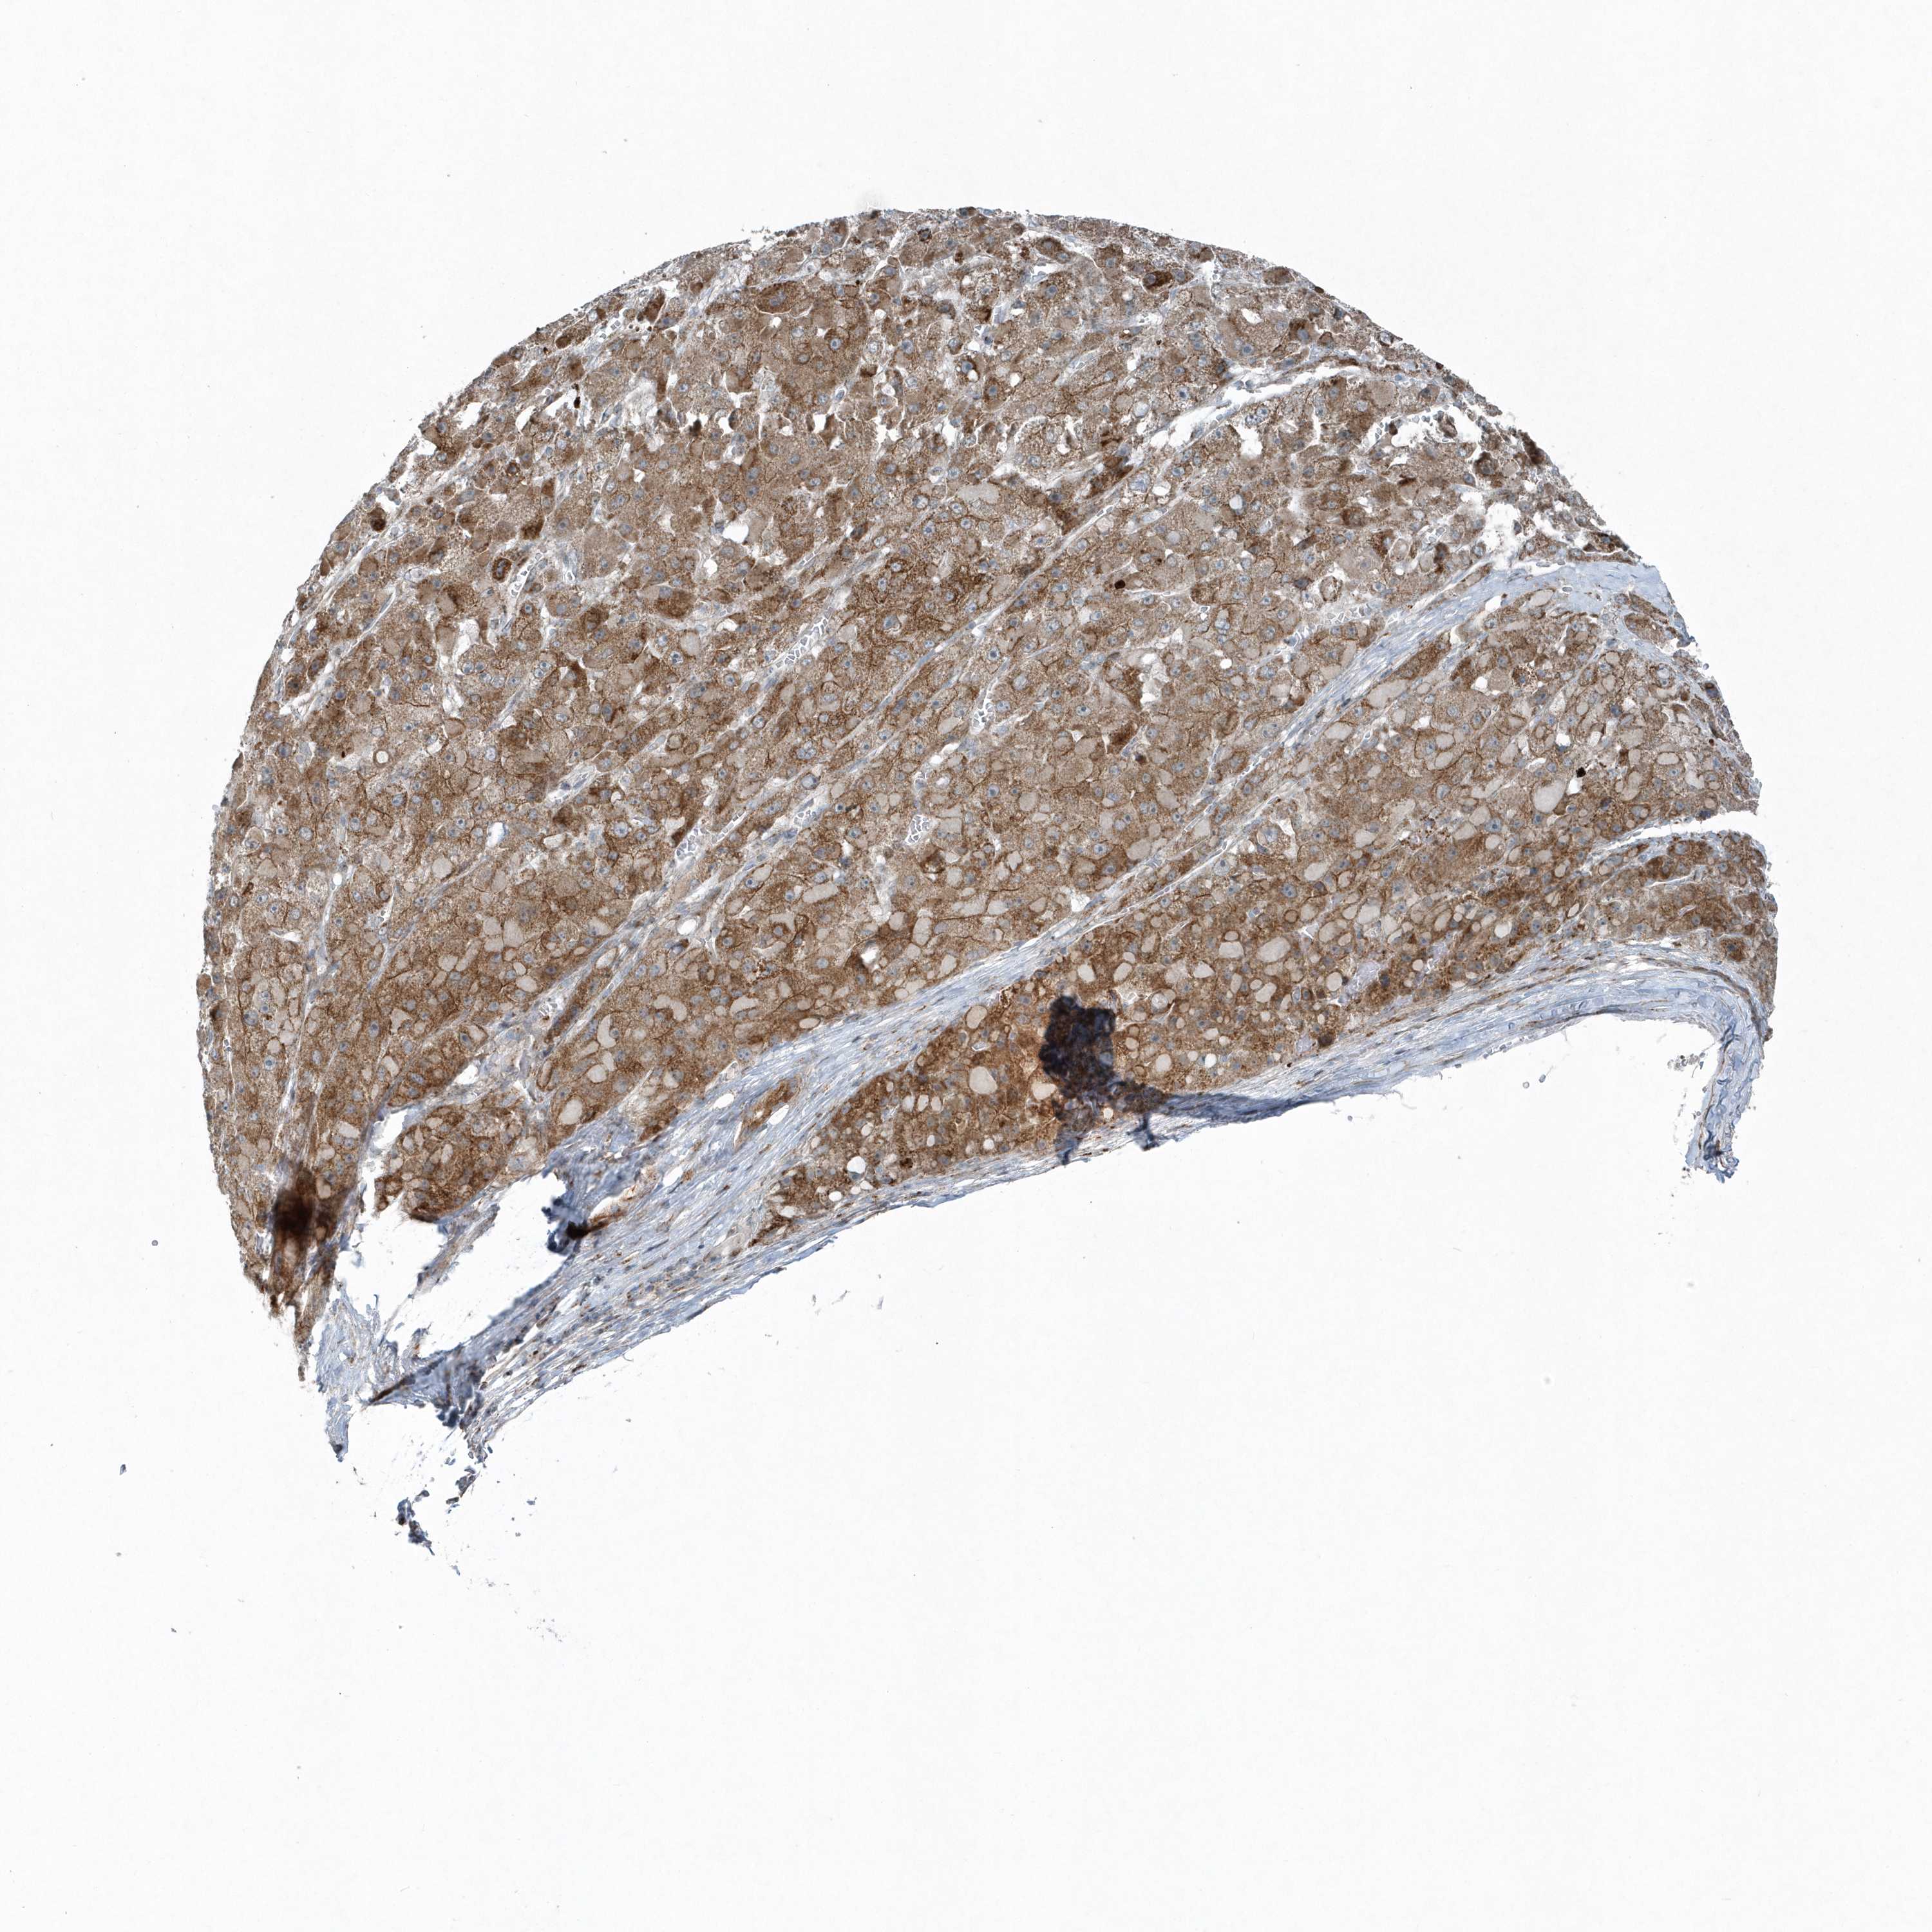

LIVER CANCER - Protein expressioni

A mouse-over function shows sample information and annotation data. Click on an image to view it in a full screen mode. Samples can be filtered based on level of antibody staining by selecting one or several of the following categories: high, medium, low and not detected. The assay and annotation is described here.

Note that samples used for immunohistochemistry by the Human Protein Atlas do not correspond to samples in the TCGA dataset.

Antibody stainingi

Antibody staining in the annotated cell types in the current human tissue is reported as not detected, low, medium, or high, based on conventional immunohistochemistry profiling in selected tissues. This score is based on the combination of the staining intensity and fraction of stained cells.

Each image is clickable and will lead to virtual microscopy that enables deeper exploration of all samples and also displays staining intensity scores, fraction scores and subcellular localization as well as patient and tissue information for each sample.

Antibody HPA035849

Antibody HPA035850

Staining

High

Medium

Low

Not detected

Intensity

Strong

Moderate

Weak

Negative

Quantity

>75%

75%-25%

<25%

None

Location

Nuclear

Cytoplasmic/membranous

Cytoplasmic/membranous,nuclear

Cholangiocarcinoma

Carcinoma, Hepatocellular, NOS